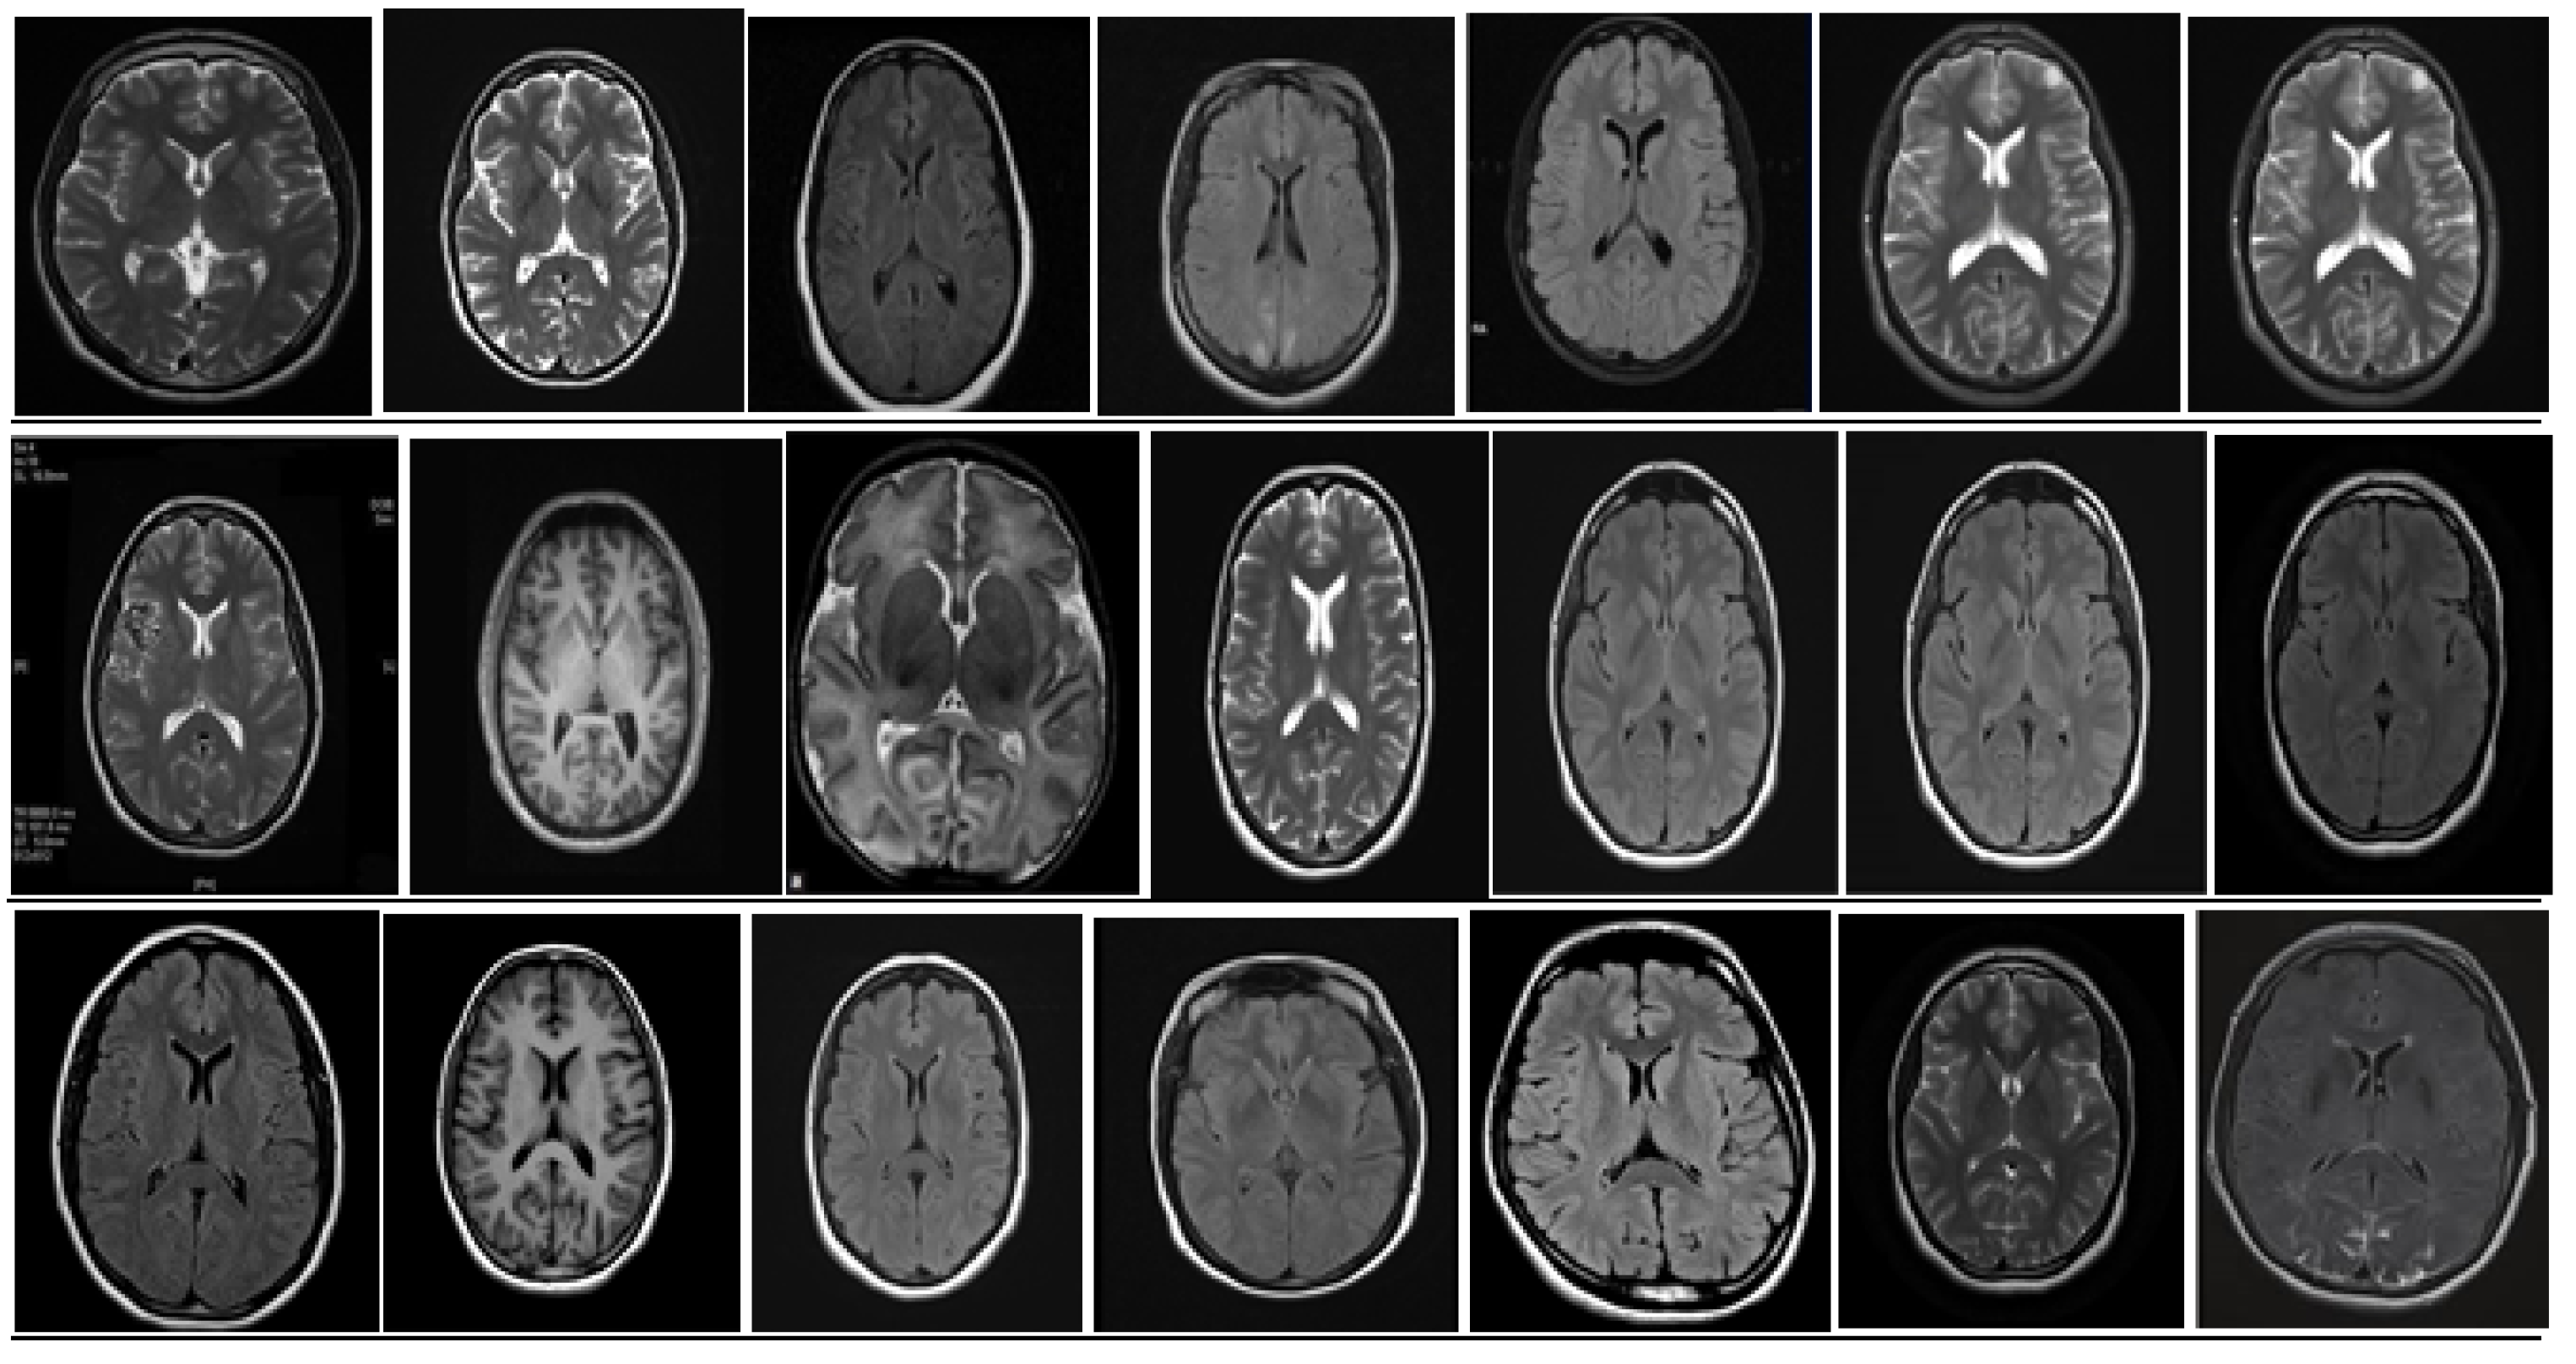

5. Database and Dataset

5.1. DataBase Collection